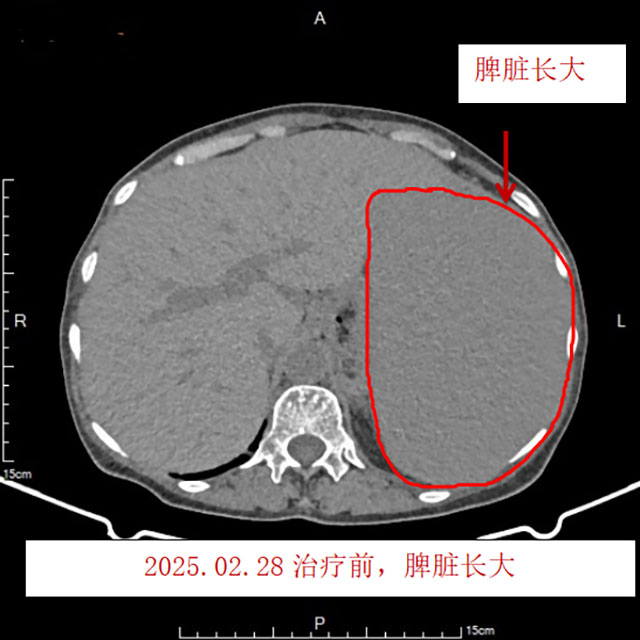

今年2月,曾婆婆来到西南医科大学附属中医医院就诊,血常规检查提示:重度贫血、血小板减少、白细胞升高;胸腹部CT检查结果提示:多发淋巴结增大、肝脏长大、脾脏长大,行骨髓穿刺及活检后,确诊为套细胞淋巴瘤(IV期,MIPI评分9分,高危)。

治疗后血小板恢复正常,心累、气促、乏力、汗多、潮热、双下肢水肿等症状均缓解,复查胸腹部CT发现淋巴结、肝脏、脾脏均较前明显缩小,复查骨髓未见异常B淋巴细胞。